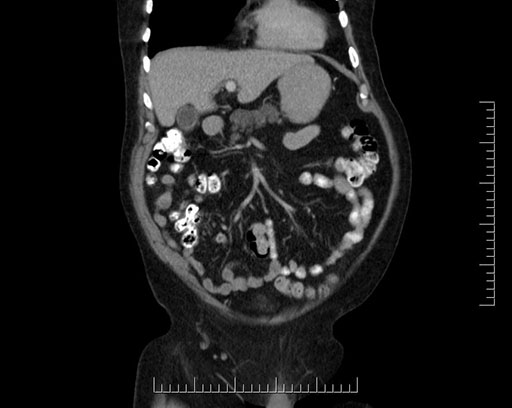

Coronal - stented